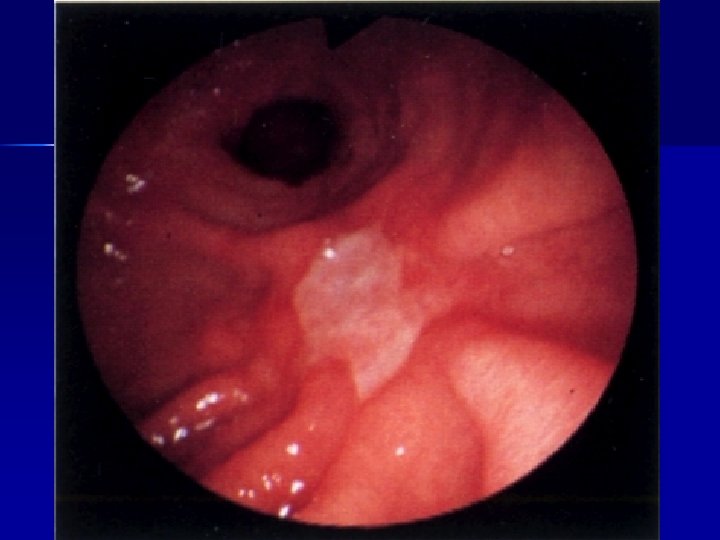

ENDOSCOPIA Lesioni del basso esofago n Patologia gastroduodenale(gastrite, ulcere, ernia iatale, corpi estranei) n Patologia rettocolica (colite ulcerosa, aspecifica, allergica, m. di Chronn) n